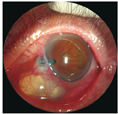

患者男,57岁。2014年1月于河南省立眼科医院就诊,1个月前,自觉左眼异物感,视力下降,并发现左眼泡样隆起物,来我院就诊。追问病史,患者30年前左眼曾被扫帚击伤,未行手术治疗,全身及局部应用药物治疗,视力稍有下降。本次入院检查:视力:右眼0.8,左眼0.1;眼压:右眼16 mmHg,左眼15 mmHg。左眼鼻下方球结膜可见巨大泡样隆起,壁薄,6点至9点位角巩膜缘处可见巩膜葡萄肿,余角膜透明,前房中深,瞳孔呈梨形,向鼻下方移位明显(图1)。左眼UBM检查角膜回声清晰,中央前房深2.4 mm,瞳孔向鼻侧移位,8点位角巩膜缘处连续性中断,断口直径约0.57 mm,缺损处上方少部分向前房内弯曲,对应处见巨大结膜滤过泡,与前房沟通,呈分叶状(图4)。左眼B超见玻璃体混浊。根据患者外伤史及检查所见,诊断为:左眼前巩膜葡萄肿伴巨大滤过泡,入院行异体巩膜移植术。手术方法:因滤过泡与前房沟通,为避免切开滤过泡时眼压骤降,先行前房穿刺,降低眼压,沿角膜缘剪开鼻下方球结膜,暴露巩膜葡萄肿,发现8点处角巩膜缘穿孔,虹膜嵌顿,与周围组织粘连较重,去除虹膜表面结膜上皮,回纳部分虹膜,板层剖切穿孔周围巩膜,取相应大小异体巩膜植片间断缝合于巩膜植床。术后第3天:球结膜充血水肿,角膜透明,前房中深,瞳孔不规则,直径约4 mm(图2)。复查UBM见左眼角膜回声清晰,中央前房深2.6 mm,角巩膜未探及低回声区(图5)。术后取剖切巩膜病理检查示:巩膜穿孔,可见虹膜组织粘连,符合葡萄肿改变(图3)。